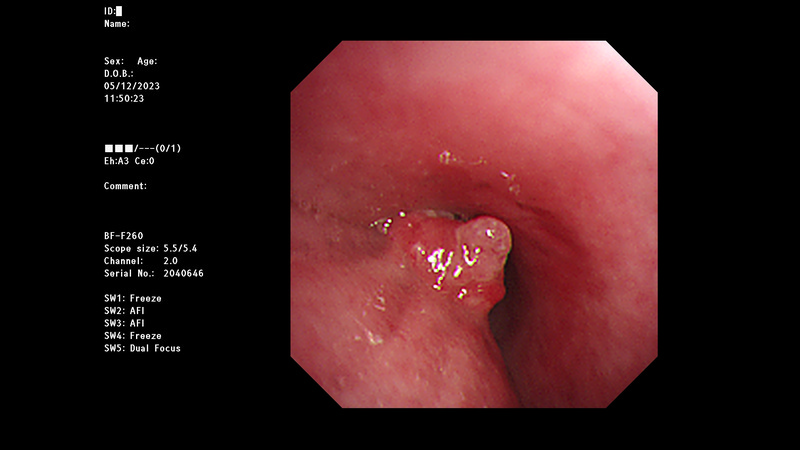

即使是第四期食道癌患者,也不是完全沒有希望。徐中平副院長指出,經過適當的治療,有些患者的病情依然可以獲顯著的改善,甚至可以達到手術治療的條件;曾有左主支氣管受腫瘤侵犯的55歲男性,經放射及化學治療後,病理報告顯示病灶顯著縮小,且無淋巴轉移。他除了建議年過四十的民眾定期健檢之外,一旦有吞嚥卡卡感覺等症狀時,務必就醫檢查,早期診斷、治療,對病人幫助最多,且大大提高成功治療的機率。

圖:圖為55碎食道癌患者,放化療前上支氣管鏡檢查,發現左側主支氣管有腫瘤侵犯。(徐中平提供)